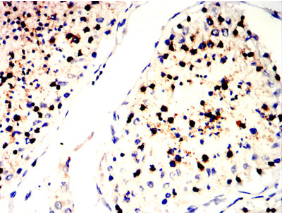

| AC3520 | SLC7A3 Mouse Monoclonal antibody[6H3B7] | 100ug | $367 | 10days |

| AC3520 | SLC7A3 Mouse Monoclonal antibody[6H3B7] | 200ug | $660.6 | 10days |